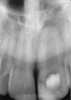

Clinical procedure: If apical bone loss is present (Figure 1) a collagen/gelatin sponge (eg, Gelfoam®, Pfizer Inc., www.pfizer.com) can be placed apically so that the MTA can be delivered to the desired working length. (Any other surgical resorbable sponge would also work, such as OraPlug® [Salvin Dental Specialties, www.salvin.com], Surgifoam® [Midwest Dental, www.mwdental.com], or Surgispon® [Aegis Lifesciences, www.surgispon.com]). This is done by taking a small piece (2 mm x 2 mm) of the resorbable sponge and pushing it down to and through the root apex with an endodontic file. Once this is done, MTA is packed down the canal with a custom-fitted cone. The clinician can use a rubber stopper on the gutta-percha cone to know the exact length of MTA placed in the apical third (Figure 2). Once the apical third is sealed with 3 mm to 5 mm of MTA, the remaining coronal canal space can be back-filled using a warm gutta-percha technique (Figure 3).